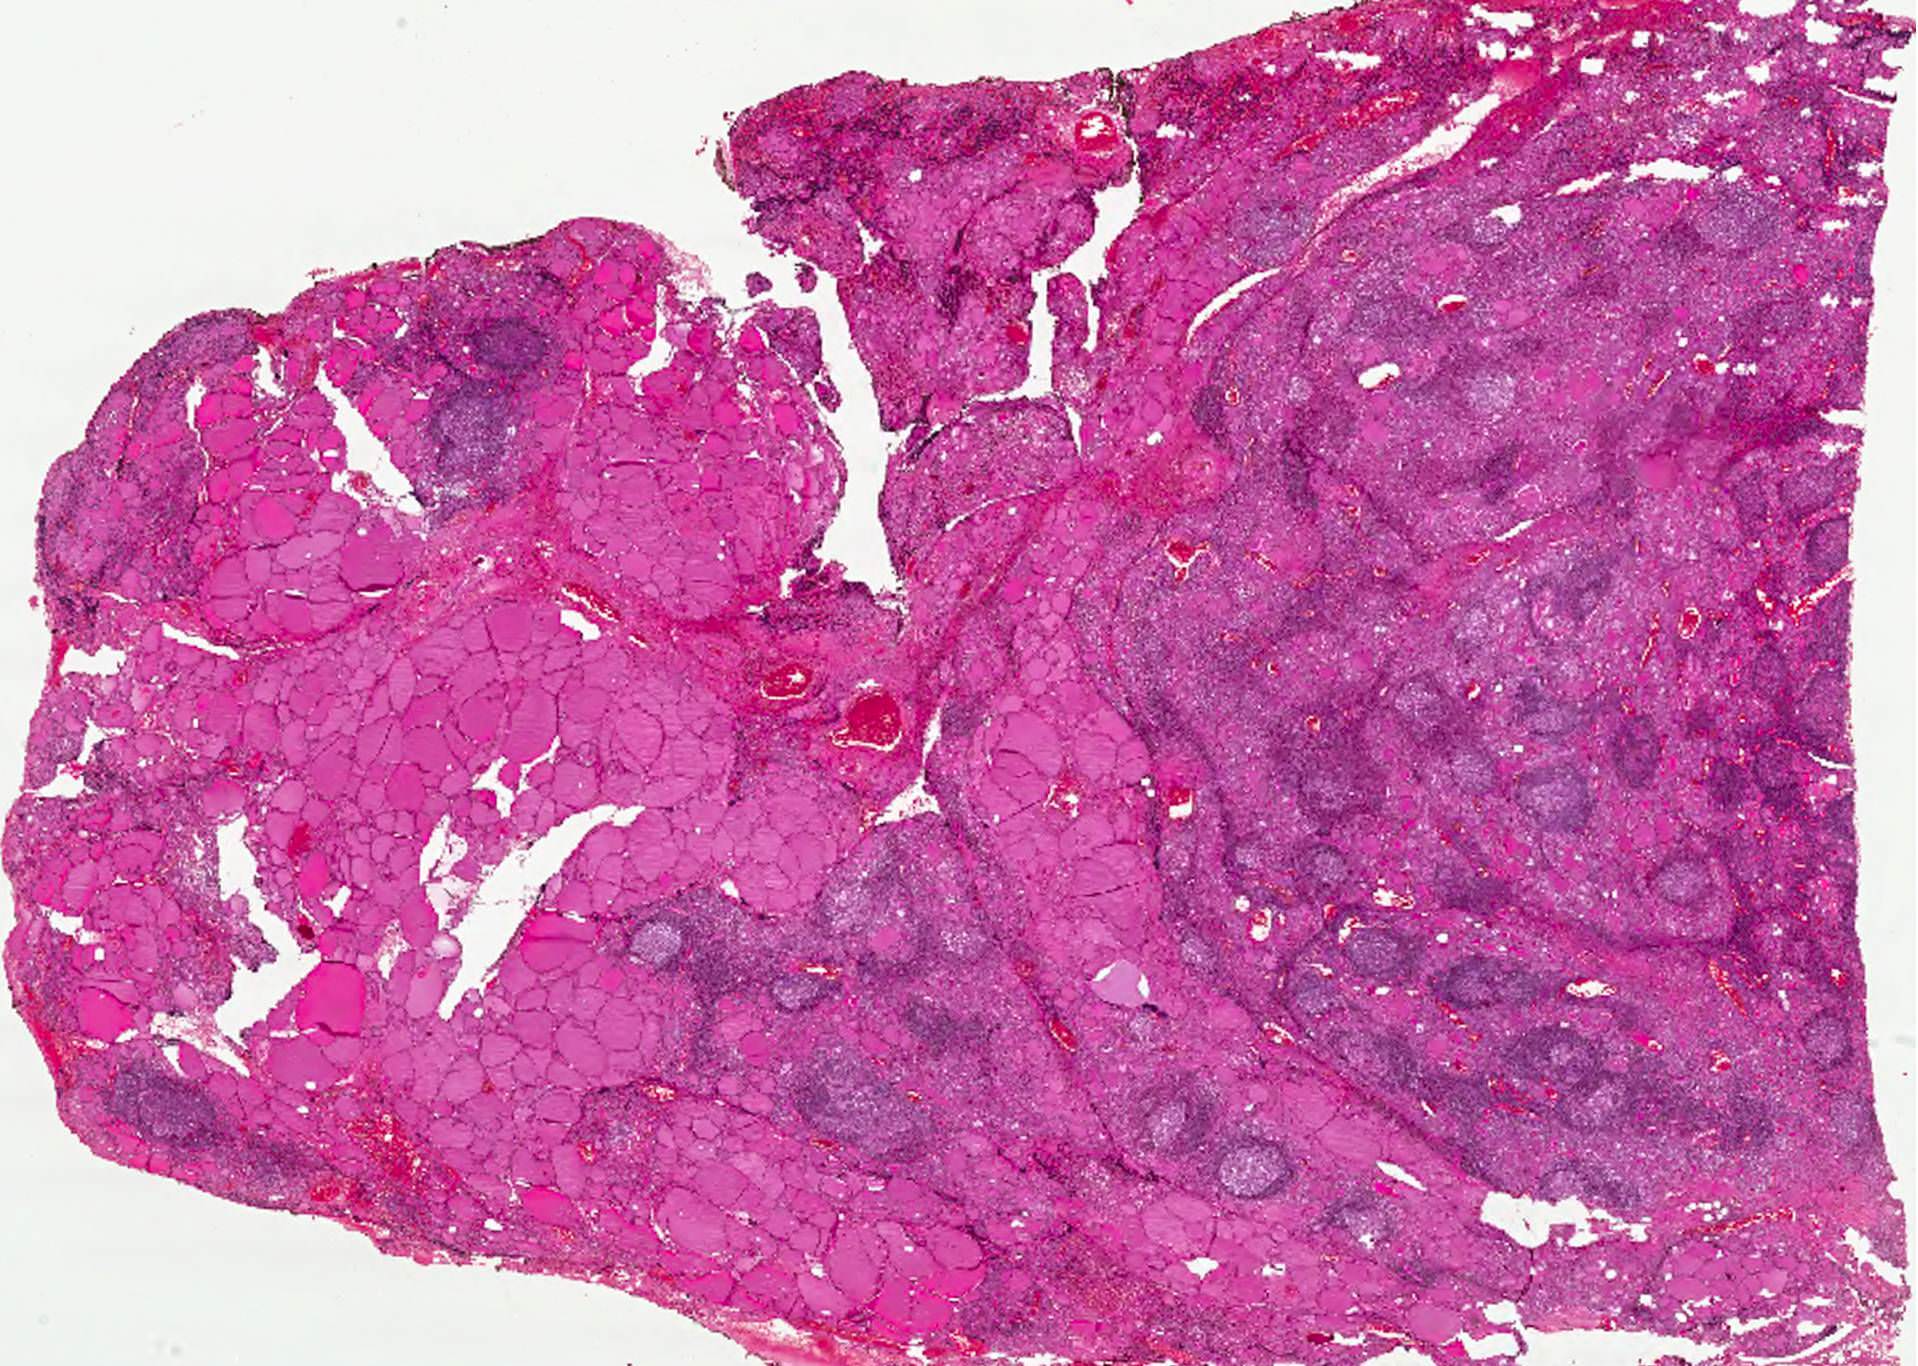

Microscopic (histologic) description

- Classic form: diffuse infiltration of thyroid parenchyma with lymphocytes and plasma cells; lymphoid follicle formation with germinal centers (Best Pract Res Clin Endocrinol Metab 2019;33:101367)

- Polymorphic lymphocytic infiltrate, predominantly T cells

- Thyroid follicular destruction

- Atrophic thyroid follicles; many lined by oncocytic cells / oncocytes having abundant granular eosinophilic cytoplasm; rarely squamous metaplasia

- Later fibrosis and nodularity (Virchows Arch 2013;462:557)

- Fibrous (or fibrosing) variant: extensive keloid-like fibrosis of thyroid parenchyma, fibrous septa divide the parenchyma into lobules, mononuclear cell infiltration, lymphoid follicles, thyroid follicular atrophy, oncocytic cell and squamous metaplasia (Autoimmun Rev 2014;13:391)

- IgG4 related variant: dense lymphoplasmacytic infiltrate, enriched in IgG4 producing plasma cells (> 20 cells per high power field); interstitial fibrosis; often associated with obliterative phlebitis (Autoimmun Rev 2014;13:391)

- Juvenile thyroiditis, Hashitoxicosis and painless thyroiditis: rare / absent germinal center formation and follicular atrophy, follicular cell hyperplasia, less pronounced oncocytic cell metaplasia and fibrosis (Autoimmun Rev 2014;13:391)

- Variable atypia of follicular cells and oncocytic cells, may mimic and act as a precursor (limited evidence) of papillary thyroid carcinoma (Endocr Pathol 2021;32:368)

- Squamous metaplasia of follicular epithelium can be confused with solid cell nests (J Clin Endocrinol Metab 2012;97:2209)

- May be associated with colloid goiter, follicular neoplasm, oncocytic cell neoplasm, papillary thyroid carcinoma and primary thyroid lymphoma (Acta Cytol 2009;53:507, Front Oncol 2017;7:53)

Microscopic (histologic) images

Contributed by Andrey Bychkov, M.D., Ph.D. and Shipra Agarwal, M.D.